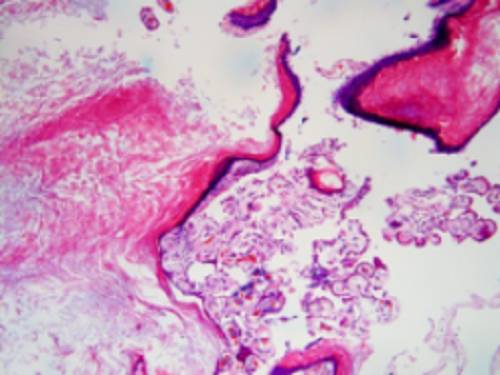

术后病理报告:腰4椎管内肿瘤:良性病变,可见纤维组织、钙化、少量角化物及胆固醇结晶沉积,无明确上皮,符合表皮样囊肿(图3)。

图3. 病理所见:角化性鳞状上皮,内含角化物,伴有慢性炎症细胞,胆固醇裂隙和异物巨细胞性肉芽肿。上图显示有明显钙化。

病理诊断上,表皮样囊肿由囊壁和囊内容物构成。囊壁内侧常被覆复层鳞状上皮构成的上皮衬里,外侧为纤维结缔组织构成的囊壁,囊壁内一般无皮脂腺、汗腺、毛囊等皮肤附属器。囊内充满皮脂样物并可有少量钙化物。囊肿往往随着上皮衬里细胞的增生和(或)囊肿内角化碎片的脱落而有逐渐增大的倾向。本病例肿瘤组织病理提示纤维组织、钙化、少量角化物及胆固醇结晶沉积,无明确上皮,符合表皮样囊肿。